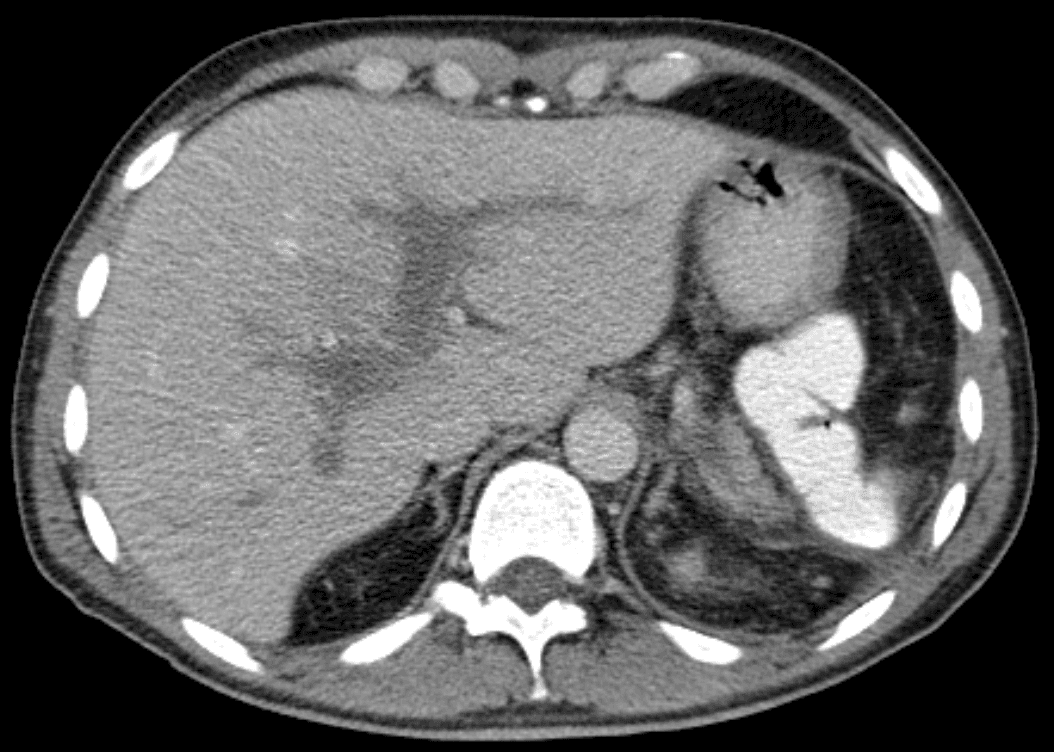

Portal vein thrombosis (PVT) is a vascular disease of the liver that occurs when a blood clot occurs in the hepatic portal vein, which can lead to increased pressure in the portal vein system and reduced blood supply to the liver. The mortality rate is approximately 1 in 10. An equivalent clot in the vasculature that exits the liver carrying deoxygenated blood to the right atrium via the inferior vena cava, is known as hepatic vein thrombosis or Budd-Chiari syndrome. Portal hypertension#Signs and symptomsPortal vein thrombosis causes upper abdominal pain, possibly accompanied by nausea and an enlarged liver and/or spleen; the abdomen may be filled with fluid (ascites). A persistent fever may result from the generalized inflammation. While abdominal pain may come and go if the thrombus forms suddenly, long-standing clot build-up can also develop without causing symptoms, leading to portal hypertension before it is diagnosed. Other symptoms can develop based on the cause. For example, if portal vein thrombosis develops due to liver cirrhosis, bleeding or other signs of liver disease may be present. If portal vein thrombosis develops due to pylephlebitis, signs of infection such as fever, chills, or night sweats may be present. Slowed blood flow due to underlying cirrhosis or congestive heart failure is often implicated. The prevalence of PVT in patients with cirrhosis is unclear, with a wide variety of incidence claimed by various researchers (estimated to be 1 in 100 by some while others believe it affects nearly 1 in 4). Thrombophilia (including inherited conditions such as factor V Leiden deficiency, protein C or S deficiency, or antiphospholipid antibody syndrome) is another common cause. Nearly one-third of patients have a myeloproliferative disorder (e.g. polycythemia vera or primary thrombocytosis), most commonly due to a Janus kinase 2 (JAK2) gene mutation. Oral contraceptive use or pregnancy are other non-inherited tendencies for thrombosis.